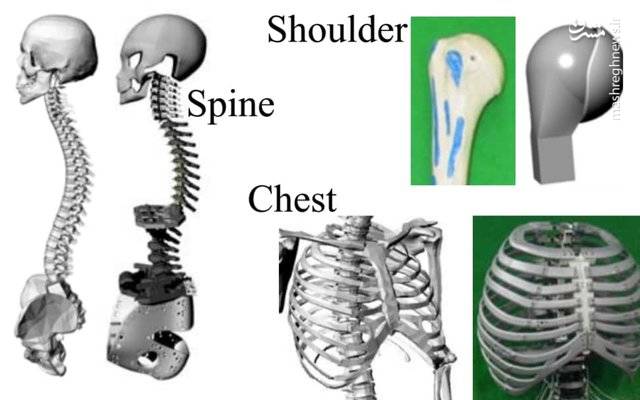

آناتومی سه بعدی بدن انسان عکس گرافی بدن.

اسکلت داربست بدن است تمام قسمت های بدن روی اسکلت قرارگرفته اند بدن انسان از ۲۰۶ قطعه استخوان تشکیل شده است این استخوان ها طوری با نظم کنار هم قرار گرفته اند که انسان را قادر می سازد حرکات دقیقی داشته باشد. استخوان یک نسج بسیار محکم است زیرا در ترکیب آن منرالها مانند کلسیم و دیگر وجود. اسکلت داربست بدن است تمام قسمت های بدن روی اسکلت قرارگرفته اند بدن انسان از ۲۰۶ قطعه استخوان تشکیل شده است این استخوان ها طوری با نظم کنار هم قرار گرفته اند که انسان را قادر می سازد حرکات دقیقی داشته باشد. آناتومی سه بعدی بدن انسان عکس گرافی بدن امعاء و احشاء بدن آناتومی سه بعدی بدن انسان عکس گرافی بدن امعاء و احشاء بدن قلب کبد روده.